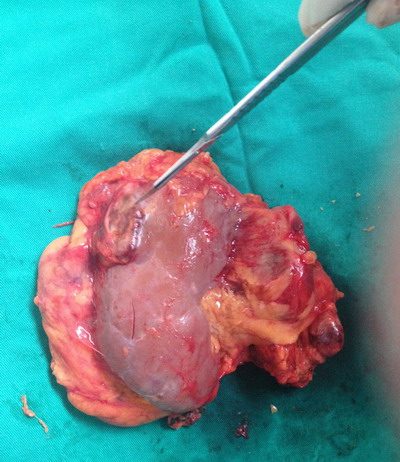

- Loạn sản dạ dày mức độ nặng (Hình 41): Thường gặp ở các thể viêm, loét...